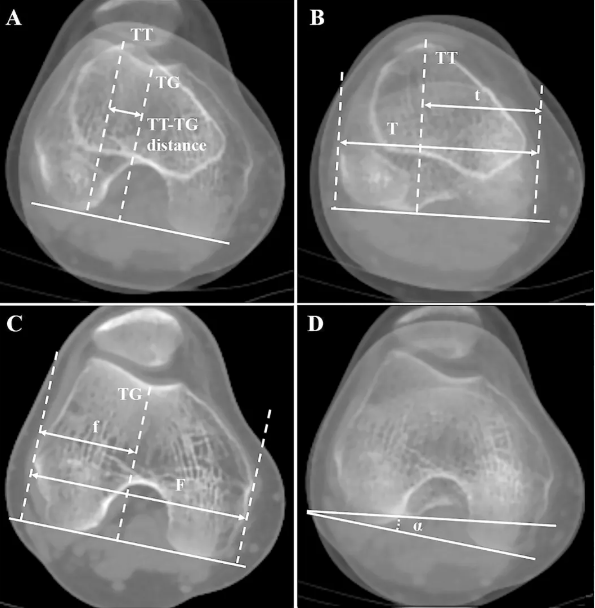

(3)胫骨结节-股骨滑车沟距离

在CT或MRI上测量,它代表了髌腱附着点(胫骨结节)到股骨滑车沟中心的水平距离。这个距离直接反映了牵拉髌骨向外的力量(Q角的概念在影像学上的精确体现)。TT-TG距离大于20mm被视为异常,是髌骨外脱位的重要风险因素。距离越大,向外侧的拉力越大。

(4)髌骨高位

测量方法:常用Insall-Salvati指数(在侧位X光片上测量,髌腱长度与髌骨长度的比值,>1.2为高位)。 髌骨位置过高,在膝关节屈曲早期,髌骨无法及时进入相对较深的股骨滑车沟内,使其在最不稳定的阶段更容易向外脱位。